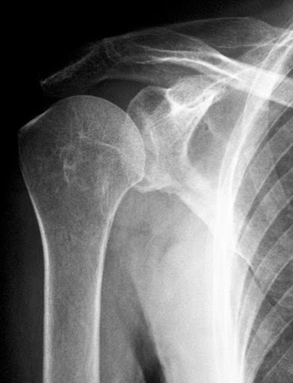

Запитання 18

РОЗПІЗНАЙТЕ НА РЕНТГЕНОГРАМІ СУГЛОБ, ЩО МАЄ МІЛКУ СУГЛОБОВУ ЗАПАДИНУ І СКРІПЛЕНИЙ ПЕРЕВАЖНО М'ЯЗАМИ, ТОМУ ТУТ ВІДНОСНО ЧАСТО БУВАЮТЬ ВИВИХИ.

варіанти відповідей

НА ЯКИЙ СУГЛОБ ВКАЗУЄ СТРІЛКА НА РЕНТГЕНОГРАМІ? КІСТКИ ЯКОГО ВІДДІЛУ СКЕЛЕТУ ВІН З'ЄДНУЄ?

ГРУДНИННО-КЛЮЧИЧНИЙ С.

ПЛЕЧОВИЙ С.

НАДПЛЕЧОВО-КЛЮЧИЧНИЙ С.

АКРОМІАЛЬНО-КЛЮЧИЧНИЙ С.

КІСТКИ ВЕРХНЬОЇ КІНЦІВКИ

КІСТКИ ТУЛУБА І ВЕРХНЬОЇ КІНЦІВКИ

ДЕ ВИ БАЧИТЕ СУГЛОБ, ЯКИЙ ЗАБЕЗПЕЧУЄ РУХИ ПЛЕЧА.